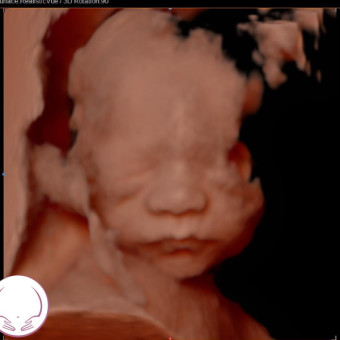

Baby Mabel “Mae” Brownhill

Megan & James Brownhill

Fort Worth, TX

June 14, 2026